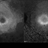

- retinitis pigmentosa, fundus photograph, infrared image, autofluorescence imaging

Scanning laser ophthalmoscope

Heidelberg HRA + OCT Spectralis - Description

- Fundus image a 57-year-old man with retinitis pigmentosa on both eyes. These image were taken with blue auto fluorescein mode (BAF) and infrared auto fluorescence (IRAF).